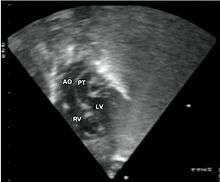

Abbreviations: LV and RV=left and right ventricle, PT=pulmonary trunk, VSD=ventricular septal defect, PS=pulmonary stenosis.

Abbreviations: RA=right atrium, RV=right ventricle, LV=left ventricle, PT=pulmonary trunk, LPA and RPA=left and right pulmonary artery.